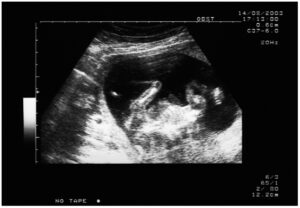

Amniocentesi: ricorrere agli antibiotici prima dell’esame potrebbe dimezzare rischi aborto

Antibiotici 'salva bebè' prima dell'amniocentesi: l'uso sempre maggiore di questi farmaci prima di eseguire l'esame ha ridotto il rischio aborto...